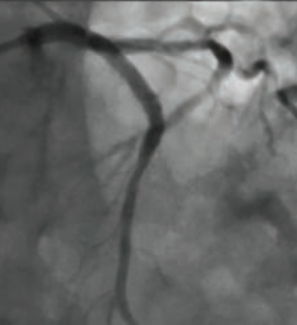

Although some of the causes of myocardial infarction with no coronary artery obstruction (MINOCA) are often unknown, spontaneous coronary artery dissection (SCAD) in MINOCA should always be considered early on as one of the major etiologies...